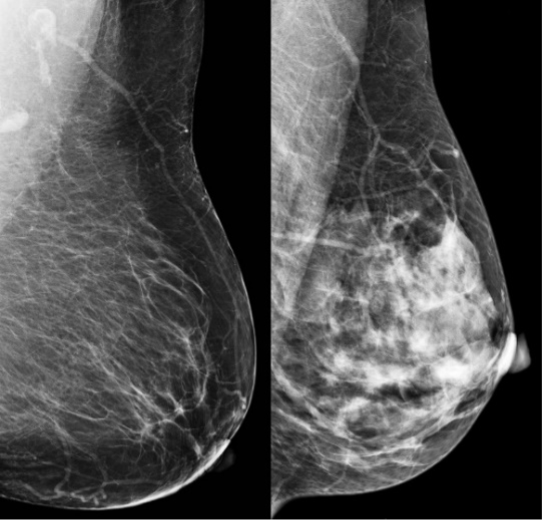

Many options are possible for identifying risk groups and then what might be offered to those risk groups. Important risk factors include high breast density (radiographically opaque breast tissue - see figure below), various genetic mutations (such as the BRCA1/2), hormonal and reproductive histories (e.g. age at first period, childbearing and breastfeeding history), alcohol consumption, some types of menopausal hormone therapy, and being overweight.

Mammograms (breast x-rays) showing low breast density (left) and high breast density (right)

Breast density is of particular interest because it is both a risk factor for breast cancer and higher breast density can also reduce the accuracy of mammograms. Some alternative breast imaging tests can be more accurate than mammography for women with dense breasts, so they are potential options for risk-based approaches to screening.